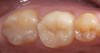

4. Bond/Seal Maintenance Risk Assessment

Figure 4  Image of preparation with poor substrate and subgingival margins where maintaining seal would be difficult. High-strength ceramics or metal ceramics would be indicated.

Figure 4